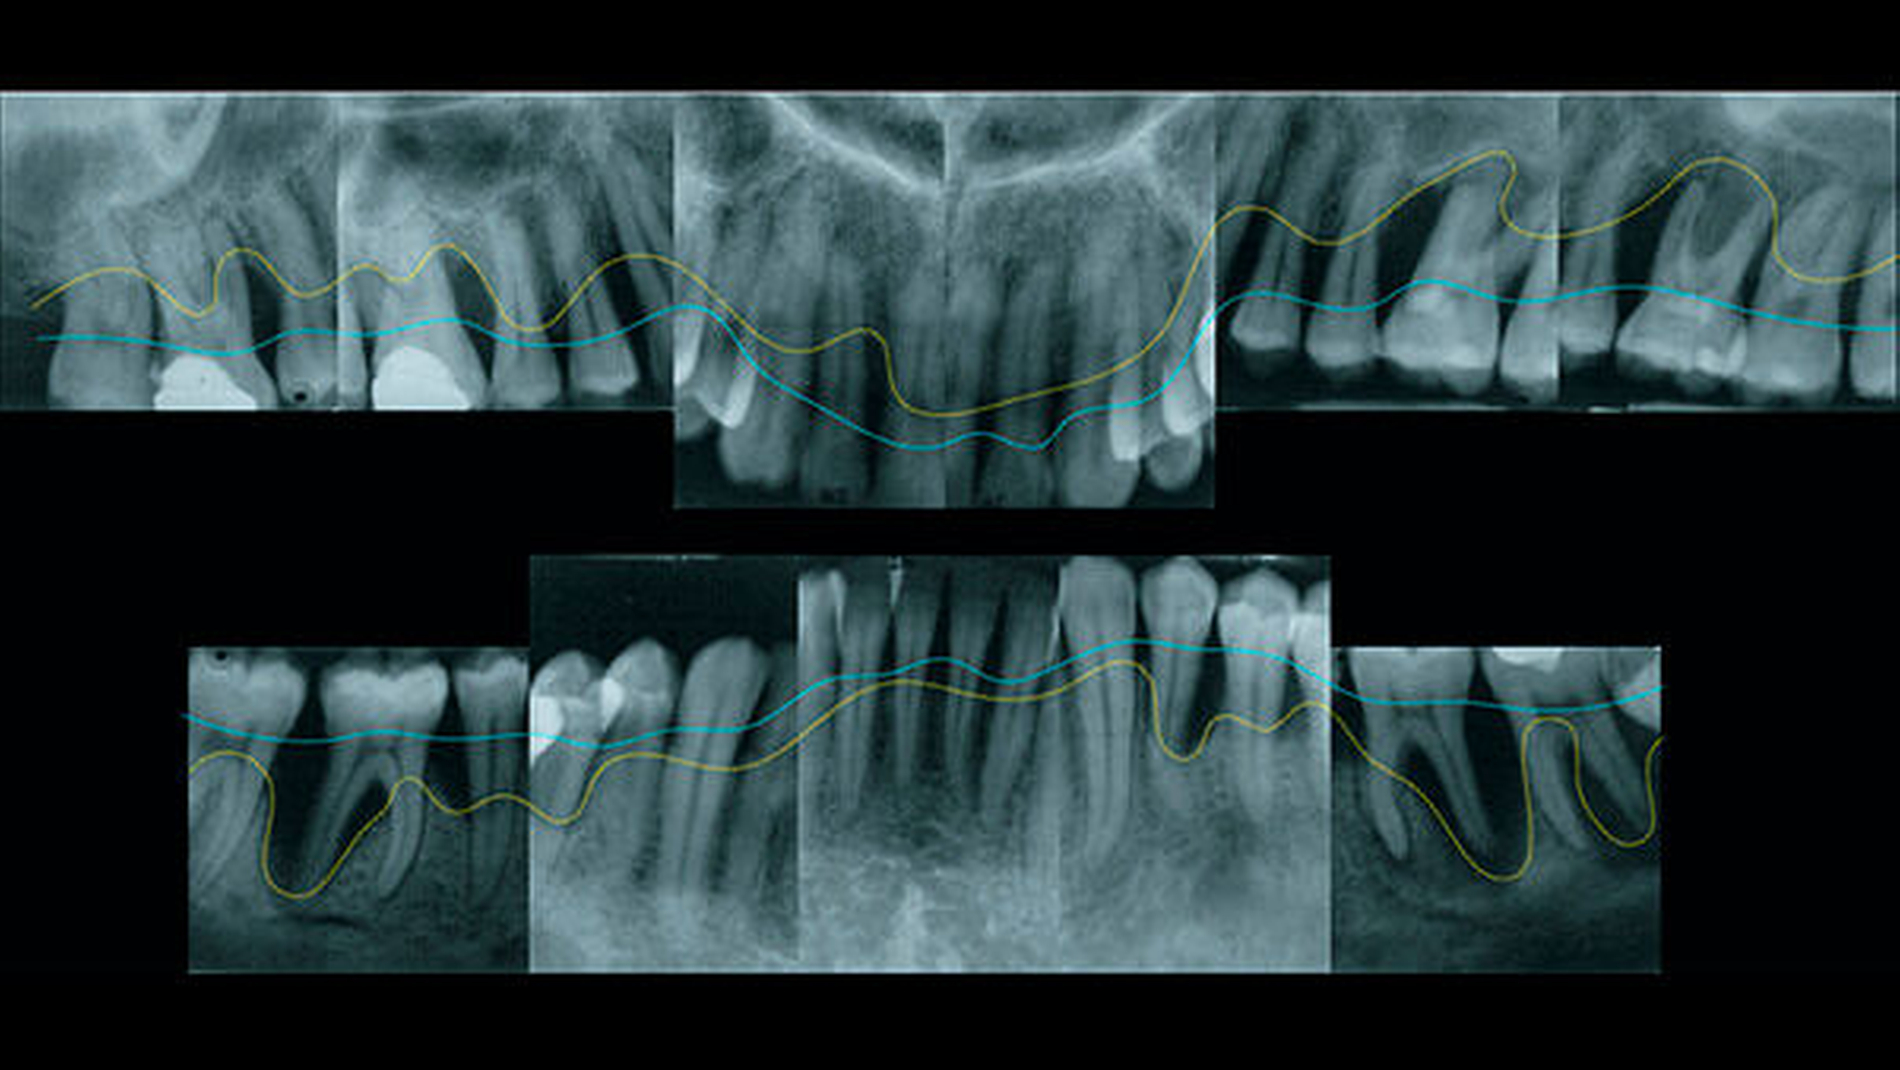

Nach ihrem klinischen Verlauf werden die seltenere aggressive (AgP) und die häufigere chronische Parodontitis (CP) unterschieden. Aufgrund der familiären Häufung, der raschen Progression und der frühen Manifestation der aggressiven Parodontitis (Abbildung 2) wird vermutet, dass genetische Faktoren für die individuelle Anfälligkeit an AgP zu erkranken eine besonders wichtige Rolle spielen. Im Gegensatz zur chronischen Parodontitis, bei der sich die negativen Effekte von Lifestyle- und Umweltfaktoren unter Umständen jahrzehntelang akkumulieren konnten, wird bei der aggressiven Parodontitis ein relativ stärkerer Anteil genetischer Einflussfaktoren vermutet (Abbildung 3). Dementsprechend wird in genetischen Studien zur Parodontitis in der Regel zunächst der Phänotyp der aggressiven Parodontitis untersucht. Genetische Forschung kann in besonderem Maß dazu beitragen, die Ursachen einer Erkrankung zu verstehen und zu erklären, warum sich Individuen in ihrer Krankheitsanfälligkeit unterscheiden, obwohl sie unter sehr ähnlichen Bedingungen leben.